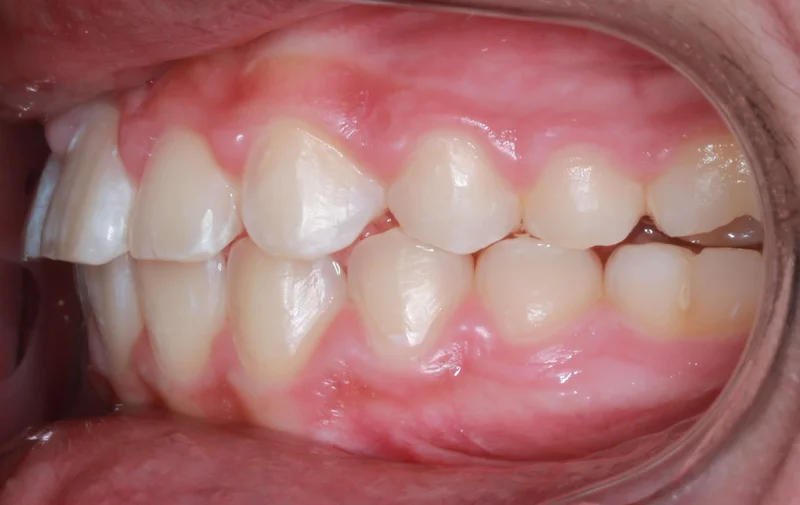

This Las Vegas teen patient presented with a moderate amount of crowding as well as deep bite and slight overbite. With proper treatment and good patient cooperation, her overbite has been corrected after 17 months of total treatment time!

Left Buccal View

Left Buccal View - Before Treatment